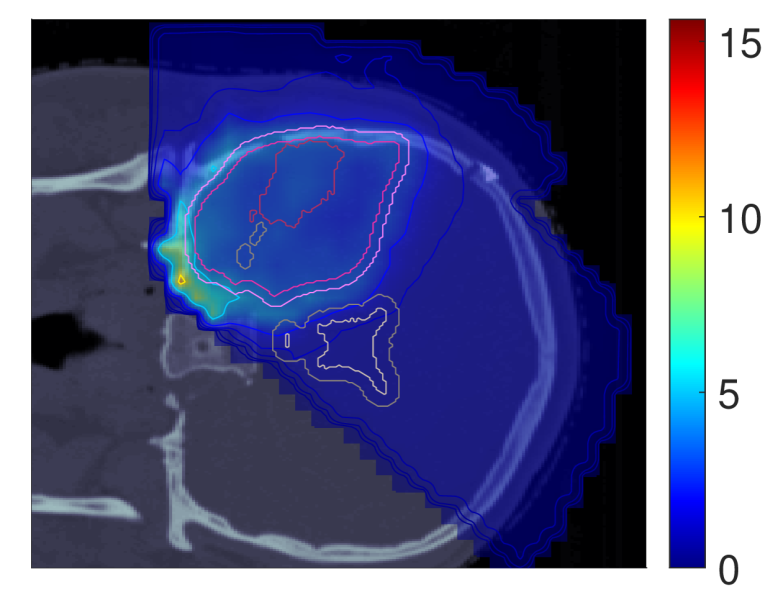

III.A.3 Probability of lesion origin pp

Figure 7 shows the POLO maps resulting from voxel-wise evaluation of the sigmoid-transformed linear predictor η\eta from Equation 1 with the input slice images for dRBE,fxd_{RBE,fx} and ldl_{d}.

NTCP30 %NTCP\approx{$30\text{\,}\mathrm{\char 37\relax}$} NTCP20 %NTCP\approx{$20\text{\,}\mathrm{\char 37\relax}$} NTCP10 %NTCP\approx{$10\text{\,}\mathrm{\char 37\relax}$}

pp (NTCPp)(NTCP_{p})

Refer to caption Refer to caption Refer to caption

pp (LSEp~)(LSE_{\tilde{p}})

pp (H~p)(\tilde{H}_{p})

pp (H~p~)(\tilde{H}_{\tilde{p}})

Figure 7: Optimal slice images of the probability of lesion origin pp for NTCPpNTCP_{p}, LSEp~LSE_{\tilde{p}}, H~p\tilde{H}_{p} and H~p~\tilde{H}_{\tilde{p}} at different NTCP levels. Considering the slice images for dRBE,fxd_{RBE,fx} and ldl_{d} from Figure 3 and Figure 5, the calculated pp values can be deduced from the prediction model. For example, hot spots are primarily found where high dRBE,fxd_{RBE,fx} values meet high ldl_{d} values, and for the voxels inside the 4 mm4\text{\,}\mathrm{mm} ventricular fringe where bb boosts the probability prediction. We take from these results that the POLO model-based optimization of the LGG sample patient’s proton plan achieves its goal, i.e., reducing pp in the region of interest.

For NTCPpNTCP_{p} and H~p\tilde{H}_{p}, we observed a (slight) reduction of dRBE,fxd_{RBE,fx} in the target volume and in the lower region overlapping with the VS, as well as a redistribution of ldl_{d} from the target volume to the margin of the PTV. Correspondingly, we see an overall reduction of pp in the target volume, together with an increasing attenuation of the hot spots around the marginal region of the PTV, and an elimination at the lower end of the VS. At strong down-regulation of the NTCP, the values are approximately one order of magnitude smaller, with peaks in the intersections to the 4 mm4\text{\,}\mathrm{mm} ventricular fringe and in regions where dRBE,fxd_{RBE,fx} and ldl_{d} intensify.

LSEp~LSE_{\tilde{p}} showed a decay of dRBE,fxd_{RBE,fx} inside but not outside the target volume, and almost constant values of ldl_{d}, and we recognize this pattern again in the pp distributions: hot spots are softened by the isolation of high-dose and high-LET regions, and the pp values in the target volume follow the negative trend for dRBE,fxd_{RBE,fx} at lower NTCP levels. Even the “dose gap” that occurs at an NTCP of 20 %20\text{\,}\mathrm{\char 37\relax} in the upper part of the target volume can be read from pp. Last, for H~p~\tilde{H}_{\tilde{p}} we can correlate the results for dRBE,fxd_{RBE,fx} and ldl_{d} again to understand pp. The higher ldl_{d} along the PTV margin is reflected by larger pp values and local hot spots, while the region around the GTV exhibits smaller pp values due to the reduction of dRBE,fxd_{RBE,fx}. At the lowest NTCP level, dRBE,fxd_{RBE,fx} contracts around the GTV, leaving only a slightly upward region at the left margin of the PTV which resembles the high-LET region, and hot spots where dRBE,fxd_{RBE,fx}, ldl_{d} and bb interact reinforcingly.

Globally, we observe an analogous shift in the “mass” of the pp distribution to lower values from the histograms in Figure 8. This indicates that the overarching goal of reducing pp during optimization can be fulfilled.